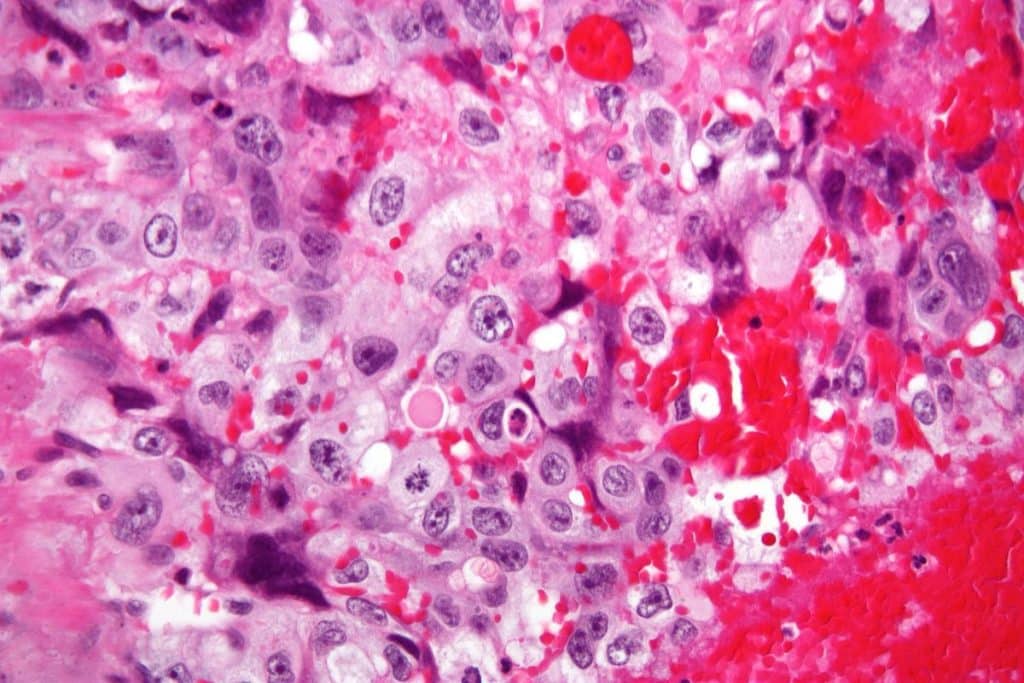

Fig 1 - High magnification image of choriocarcinoma. The cell population consists of cytotrophoblasts and syncytiotrophoblastics

High magnification image of choriocarcinoma. The cell population consists of cytotrophoblasts and syncytiotrophoblastics

• Choriocarcinoma – a malignancy of the trophoblastic cells of the placenta. It commonly, but not exclusively, co-exists with a molar pregnancy.

• This type of GTT characteristically metastasises to the lungs.